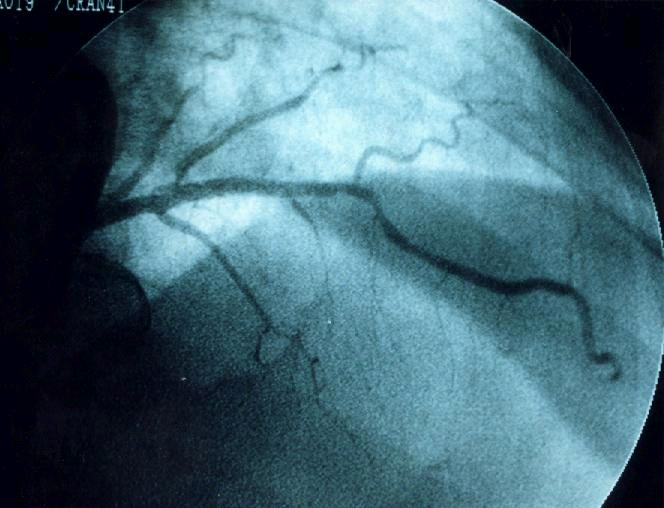

Hình 3-3. Nong và đặt Stent động mạch liên thất trước.